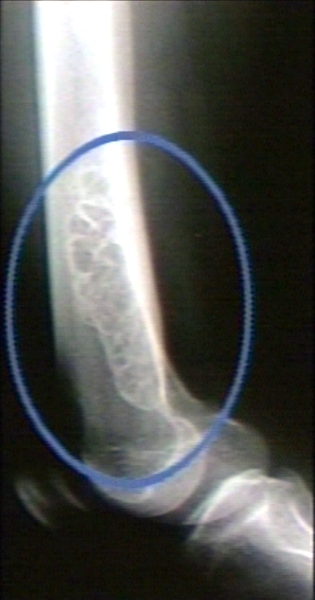

RADIOLOGY: SOFT TISSUE: FIBROMA, NON OSSIFYING FIBROMA; LATERAL VIEW (PLAIN FILM)